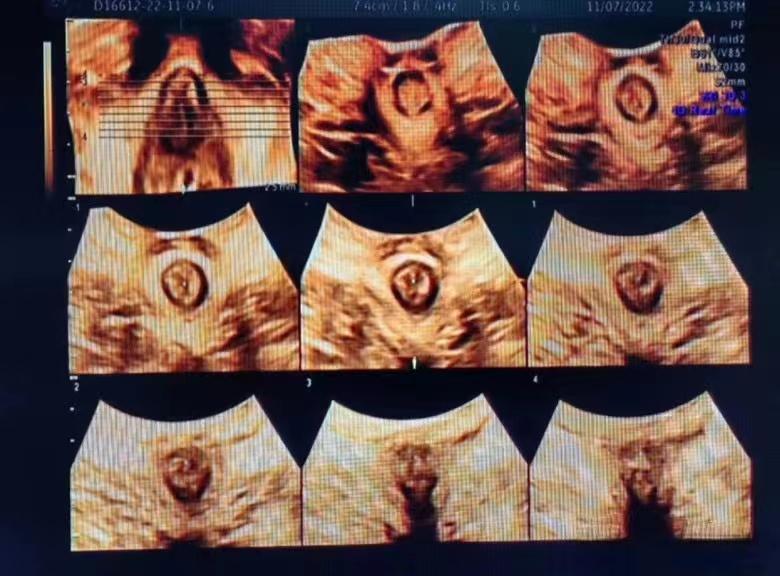

盆底超声检查可以清晰观察到盆底的解剖结构及动态变化,应用二维超声探头在会阴部观察患者盆腔前、中、后三个腔室,来了解盆底组织、器官的结构和功能,同时可以进行四维容积成像,可获得肛提肌裂孔面积,可以进行层厚约2.5mm断层成像,如同CT图像一样,一层一层扫描,从而准确判断肛提肌及肛门内外括约肌的损伤部位及程度。